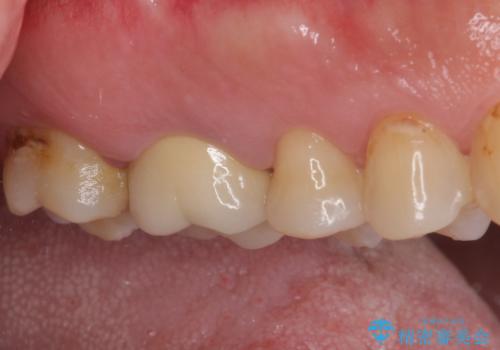

歯間ブラシを通す度に出血をするのは、ご自身の磨き方が悪いからと思っていらっしゃいましたが、治療後は全く出血することがなくなり、患者様には大変満足していただきました。